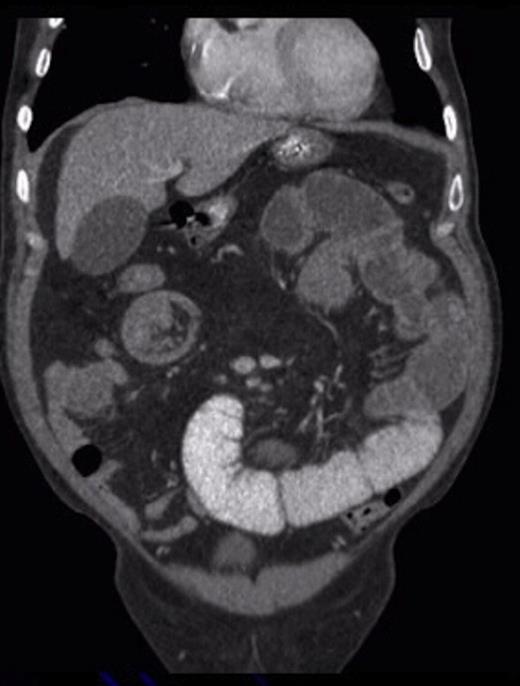

Two weeks later, he was readmitted with worsening pain and absolute constipation. Abdominal X-ray showed marked dilatation of the proximal and mid small bowel loops in keeping with high grade small bowel obstruction. CT confirmed this, demonstrating the classic donut sign on coronal reformat; the wall of the intussusception appeared thickened but no definite mass lesion was seen at this point.

Sagittal CT showing the ‘sausage’ appearance of the intussusception